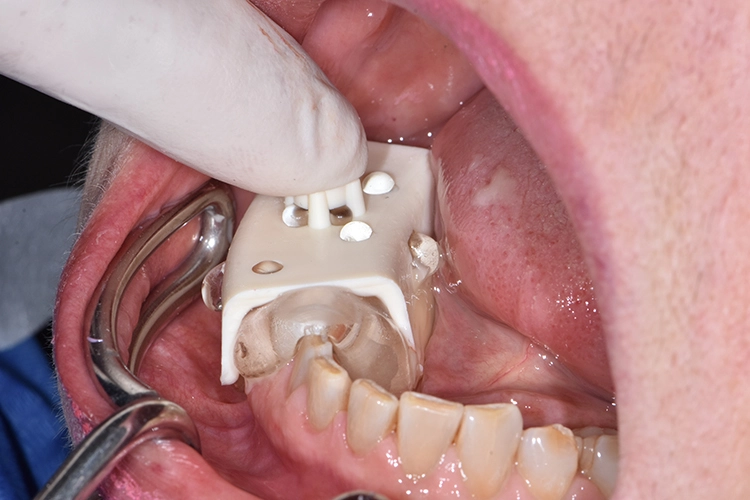

Nach der Alginat-Abformung folgte die Modellerstellung der Ausgangssituation (Abb.2). Mithilfe des Unterkiefermodells wurde ein individueller Abformlöffel mit einer Perforation im Bereich 47 für die spätere Implantat- und Pfeilerabformung angefertigt sowie eine Abformung mit EXACLEAR (GC) (Abb. 3) für die provisorische Versorgung der Zähne 45 und 46 – letzteres mittels handelsüblichem partiellen Abformlöffel.

Bilder: Dr. Lampson / HannkerHierzu wurde der Gingivaformer entfernt und ein Abformpfosten auf Implantatniveau inseriert. Retraktionsfäden an den Pfeilerzähnen 45 und 46 dienten dazu, die Präparationsgrenze aufzuzeigen (Abb. 6). Anschließend kam ein Guttapercha-Druckverband zum Einsatz, um die marginale Gingiva zusätzlich zu verdrängen (Abb. 7).